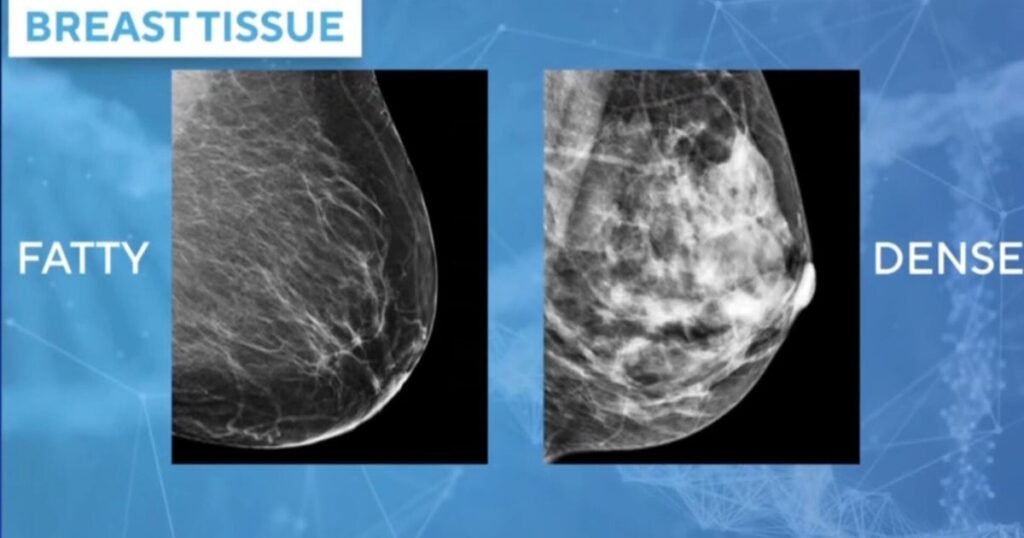

Doctors using AI mammogram readings to predict breast cancer riskDoctors using AI mammogram readings to predict breast cancer risk

Breast cancer is the second-leading cause of cancer deaths in women. About one in eight women will be diagnosed with the disease in their lifetimes. To combat that, some doctors are using AI as a tool to help them not only detect breast cancer, but also predict a woman’s risk factors. Dr. Connie Lehman, founder of Clarity, joins CBS News to discuss the first FDA-authorized AI platform used to predict a woman’s 5-year risk of developing breast cancer.